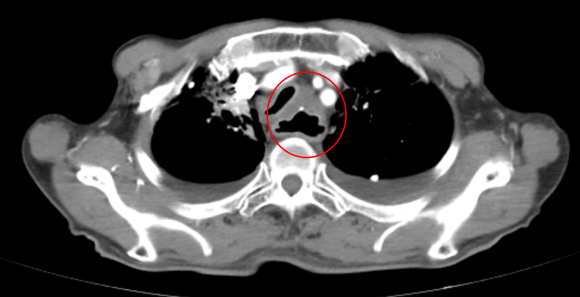

警惕饮食雷区 这些习惯可能是食管癌“元凶” 你中招了吗? 从食管的结构分布来看,主要分为颈部、胸部、腹部 3 段,而食管中的狭窄处因为直径较小,更易与食物发生摩擦,造成一定程度的机械性损伤,长此以往,这些不良饮食习惯容易引发慢性炎症或损伤,成为食管癌的幕后推手。 1、高盐饮食 长期摄入高盐食物可能导致胃酸分泌增多,增加胃黏膜的刺激,从而增加食管癌的风险。 2、腌制食品 腌制食品中含有大量的盐分和亚硝酸盐,这些物质在体内代谢产生亚硝胺类化合物,具有致癌作用。 3、热食烫饮 长期食用过热的食物或饮料可能导致食管黏膜反复烫伤,引起炎症和损伤,增加食管癌的发生风险。 4、缺乏膳食纤维 膳食纤维有助于维持肠道健康,促进肠道蠕动,减少食物在肠道中的停留时间,从而降低食管癌的风险。 总之,食管黏膜上皮肿瘤的发生是多种因素联合作用、长期慢性刺激的结果。 对于食管癌的高危人群,如年龄超过40岁、有长期吸烟饮酒史、饮食习惯不佳的人群,以及有食管癌家族史的人来说,更应该重视体检和筛查。通过定期的胃镜检查、食管细胞学检查等手段,可以及时发现食管黏膜的异常情况,从而做到早发现、早治疗。 案例分享:面对不可手术的食管癌 根治性放化疗成最后希望 * 病 情 介 绍 * 患者姓名:李先生(化名) 年龄:65岁 性别:男 诊断:食管癌(T4N1M0,ⅢB期) 临床表现: 主诉:吞咽困难,体重下降15公斤。 食管镜检查:食管中段可见肿块,阻塞大部分食管腔。 病理活检:报告为鳞状细胞癌。 CT扫描:食管中段肿块,周围淋巴结明显肿大,无远处转移。 (治疗前) 治疗方案: 鉴于患者的年龄、身体状况以及肿瘤的分期,手术切除风险较高,因此选择采用适型调强放疗(IMRT)配合化疗作为主要治疗手段。 治疗效果: 经过6周的放化疗,复查CT显示肿瘤体积显著减小,食管通畅。 随访: 治疗结束后,患者症状明显缓解,能够自行进食。 (治疗两月后食道明显扩张,进食通畅) 总的来说,对于不可手术的食管癌患者,根治性放化疗能够在最大程度上消灭肿瘤细胞,达到缩小肿瘤、疏通食管的目的,让患者重拾自主进食的能力,这不仅极大地改善了患者的营养状况和生活质量,而且在一定程度上延长了患者的生存期。